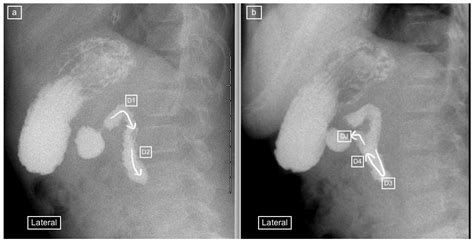

The Upper GI Series, sometimes referred to as a barium swallow or a barium meal, is a fluoroscopic examination. Unlike a static X-ray, fluoroscopy acts like a movie, allowing radiologists to observe the movement of the contrast agent as it passes through your digestive system. This dynamic view is crucial for identifying issues related to how the muscles in your esophagus and stomach are functioning, not just what the organs look like structurally.

The contrast material, a chalky white liquid containing barium, coats the lining of the esophagus, stomach, and duodenum. Because barium is a radio-opaque substance, it shows up brightly on X-ray images, providing a sharp outline of the organ walls. This makes it much easier for medical professionals to detect conditions such as ulcers, tumors, inflammation, or structural irregularities.

The procedure is generally painless and performed in a radiology department. Once you are positioned on the X-ray table, you will be given the barium contrast liquid to drink. The radiologist will instruct you to swallow it while they use the fluoroscopy machine to monitor the substance as it travels down your esophagus and into your stomach.

You may be asked to turn into different positions—such as lying on your back, side, or stomach—to ensure that the barium coats the entire surface of the stomach lining. In some instances, the doctor may also administer an effervescent powder that creates gas in your stomach to further expand the area, allowing for even clearer images, a technique often called a "double-contrast" study.